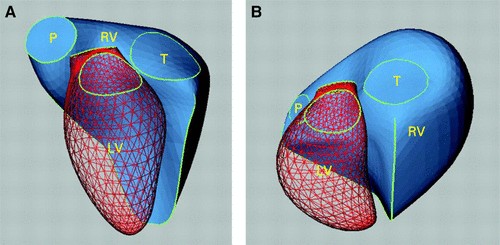

Thất phải có cấu trúc giải phẫu khá phức tạp. Về mặt hình học, thất phải là một khối hình tháp 3 mặt, ôm lấy thất trái. Ở mặt cắt trục dọc thất phải có hình tam giác, ở mặt cắt trục ngang có hình lưỡi liềm (hình 1). Thành tự do TP mỏng (2-3 mm), mềm, có độ đàn hồi cao. Cơ thất phải được tạo bởi các sợi cơ vòng ở lớp nông bên ngoài phía thượng tâm mạc và các sợi cơ dọc ở lớp sâu bên trong phía nội tâm mạc. Các sợi ở bề mặt bao vòng quanh thất phải và liên tục với các sợi cơ ở lớp nông sát thương tâm mạc của thất trái. Các sợi cơ dọc ở lớp sâu chạy dọc từ đỉnh đến đáy của tim. Thất phải co lại theo ba hướng: chuyển động vào trong buồng tim của thành tự do thất phải, sự co ngắn lại của các sợi dọc kéo mỏm tim về phía đáy của tim và lực co của thất trái. Sự co ngắn của các sợi cơ dọc đóng góp một phần lớn vào hiệu suất tâm thu của thất phải, thành phần co của thất trái đóng góp khoảng 20-40% cung lượng của thất phải [14].

Hình 1. Hình thái thất phải (RV) bình thường và bệnh lý- hình ảnh tái tạo 3D.

A- Hình thái phức tạp của thất phải ở tim bình thường. B- Tái cấu trúc thất phải gây giãn thất phải do quá tải mạn tính về thể tích hoặc áp lực trong thất phải.

(phần lưới màu đỏ là tâm thất trái (LV) và phần màu xanh đặc là thất phải (RV), P- Van ĐM phổi; T - Van ba lá). Nguồn: Sheehan và Redington